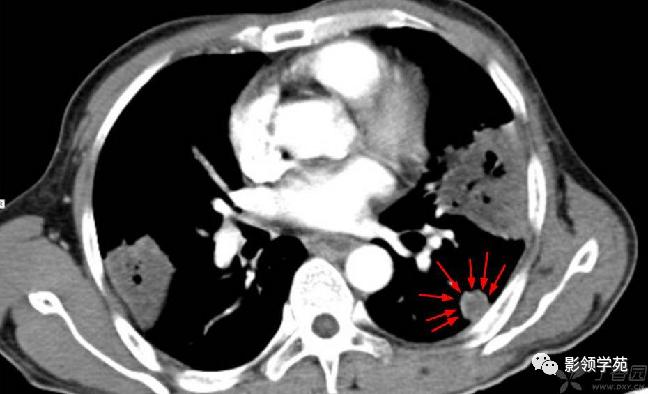

结节或肿块周围可见晕轮征、供养血管征。晕轮征提示肺结节或肿块出血,CT表现为结节或肿块周围磨玻璃密度影;供养血管征CT表现为血管影进入结节或肿块内,提示病变以血管为中心生长。

病例1:双肺多发大小不等结节,右肺中叶结节周围见晕轮征及供养血管征。

病例2:右肺下叶肿块周围见晕轮征